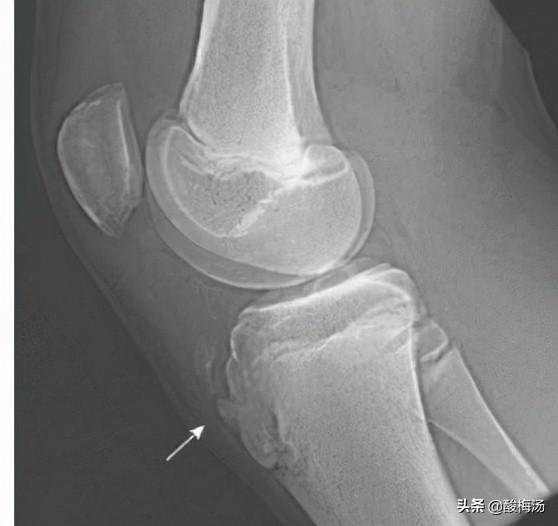

胫骨结节骨骺炎,又称胫骨结节骨软骨病,胫骨结节骨软骨炎,胫骨结节骨骺无菌性坏死。好发于青春发育期,11~15岁的男孩,多为发育加快,喜好运动者,可有剧烈运动或外伤史。胫骨结节处疼痛,活动后加重。胫骨结节局部可有肿胀,压痛,甚至红热。主动伸膝,被动屈膝或蹲起时加重,是髌腱牵拉骨骺所致。在青春发育期,股四头肌肌腱的自身发育,导致张力增加,导致胫骨结节骨骺局部炎症、肿胀,当运动时,膝关节处于屈曲位置时,股四头肌肌腱张力最大,牵拉胫骨结节骨骺,长期、反复的牵拉,对胫骨结节骨骺肯定造成进一步的损伤,慢性损伤导致进一步的缺血坏死,从而引起临床症状。这就是胫骨结节骨骺炎的发病机制。拍片时可看到胫骨结节处骨骺隆起,其间骨化不均匀,可有翘起骨片或游离骨片。